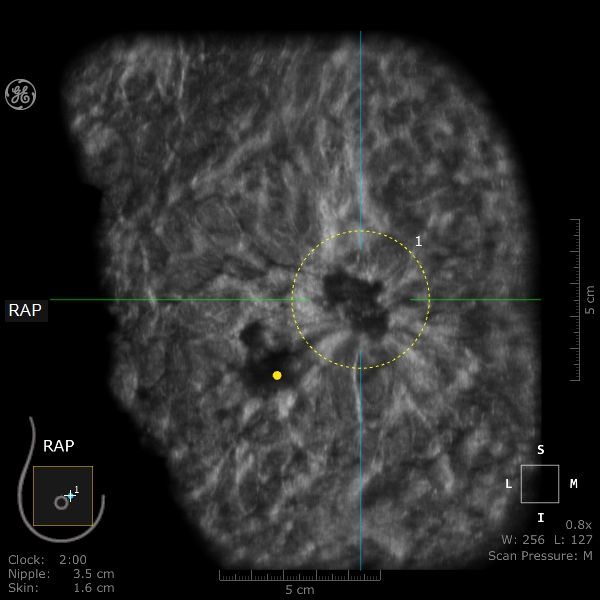

ABUS乳腺癌“汇聚征”

一次采集获得6个标准切面,采集全乳信息,可以提供手动超声不能提供的冠状面信息和容积成像,更方便临床定位和直观地提供病灶信息。

可以对多发病灶进行全面显示,不易漏诊,并且逐一描述,立体展示。什么是超声容积探头乳腺超声诊断有“神器”——自动乳腺全容积超声成像_https://www.jmylbn.com_新闻资讯_第7张

一次扫描后即可获得三切面图像——纤维腺瘤